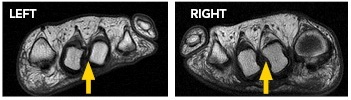

T1 weighted short axis foot MRI

The symptoms were attributed to overload metatarsalgia due to congenitally short first metatarsal bones in both feet. MRI and X-ray investigations can be seen at the right. The report verified there was no bone or joint signal typical of bone stress (or synovitis). Signal consistent with inter-metatarsal bursitis between the 2nd to 3rd inter-metatarsal space (indicated by yellow arrows). X-rays show very slight clawed second toes.